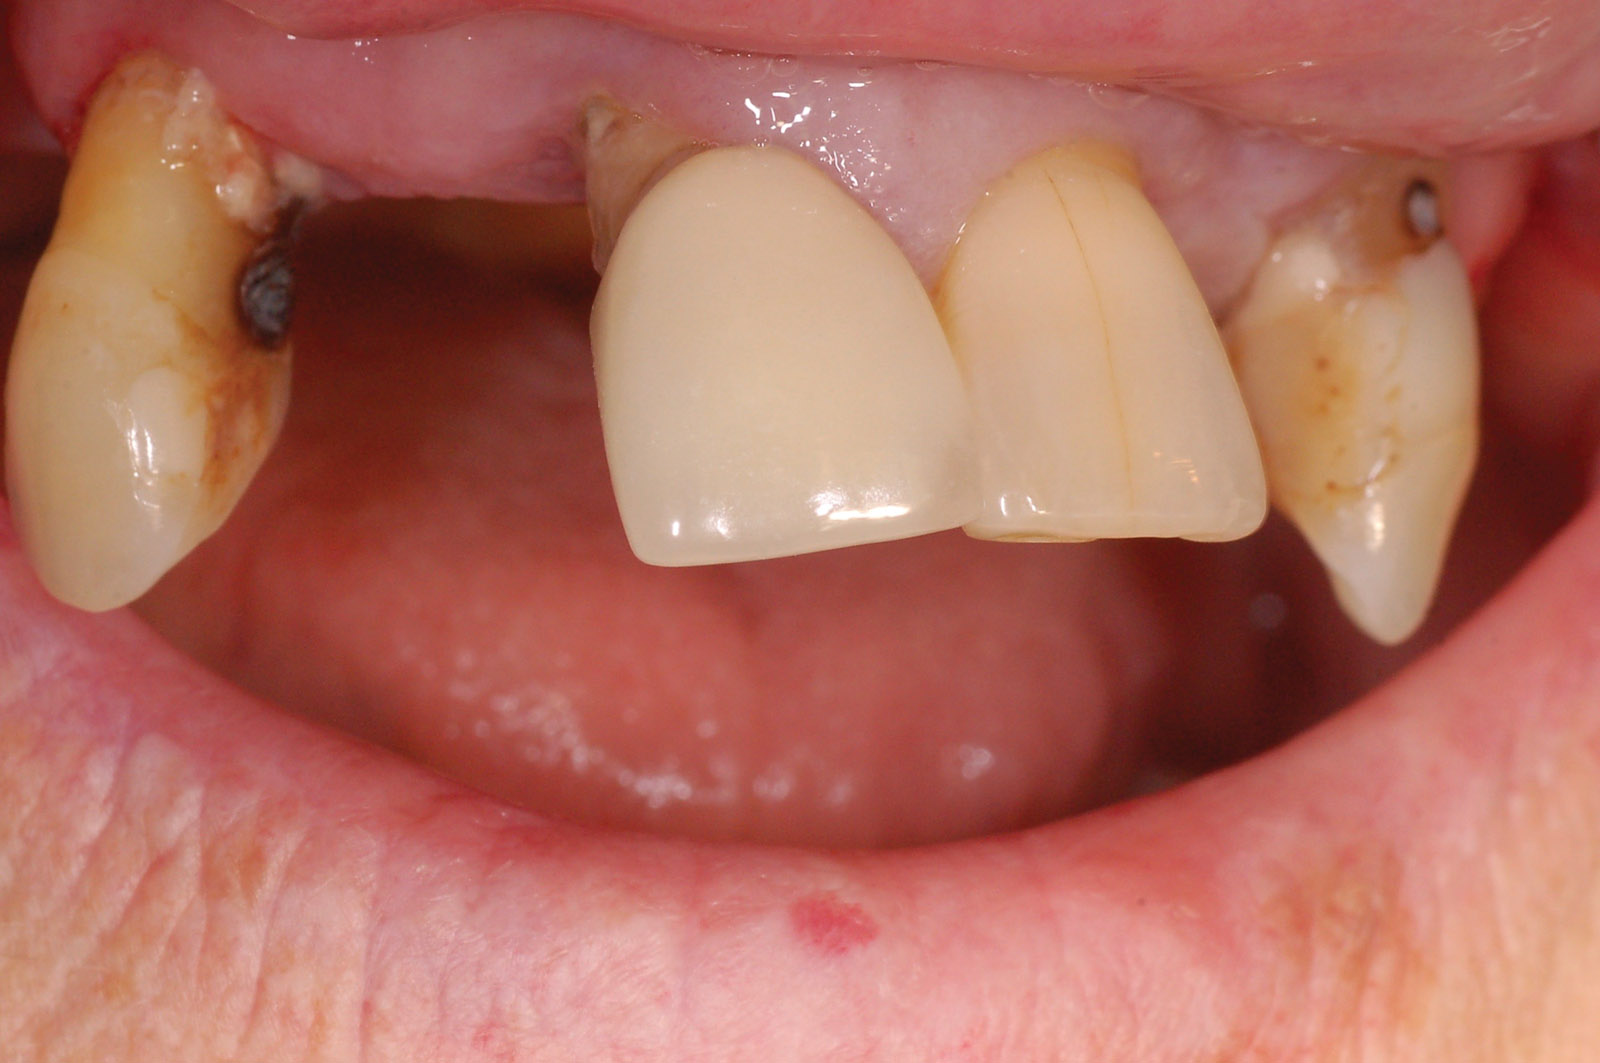

An intra-oral clinical examination was undertaken, which showed the remaining teeth had drifted and were mobile. The upper alveolar ridges had ample keratinised mucosa with adequate bone width and good bone height (Figure 2).